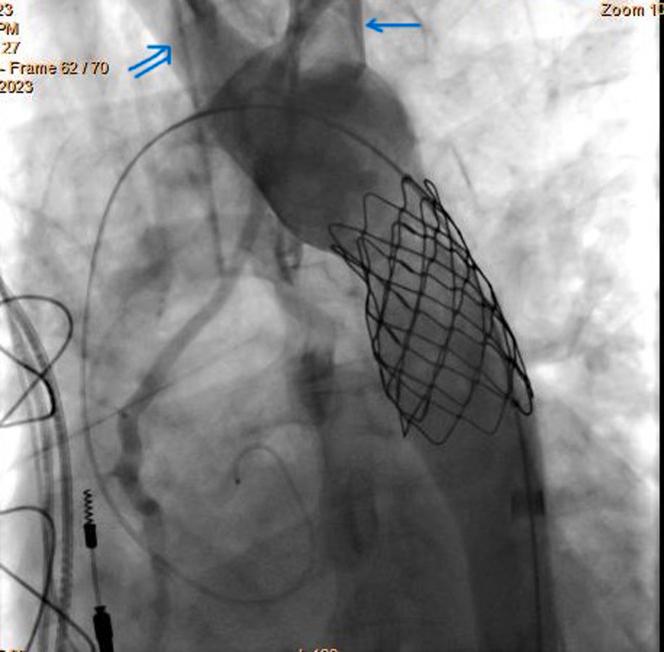

Our patient underwent surgical repair of a double-outlet right ventricle during which CoA was overlooked. She presented later with peripartum "cardiomyopathy" when CoA was diagnosed on 2-dimensional echocardiography. During transcatheter intervention, an aberrant right subclavian artery (ARSA) was seen arising before CoA opposite the origin of the left subclavian artery. The CoA was successfully treated with a bare metal stent without compromising the flow through either of the subclavian arteries.

ARSA is present in 1% of the population and usually arises distal to CoA, unlike in this case, where ARSA was proximal to the coarct.

TAKE-HOME MESSAGE: Diligent analysis of the origin of neck vessels is mandatory to plan and prevent them from jailing during stenting.